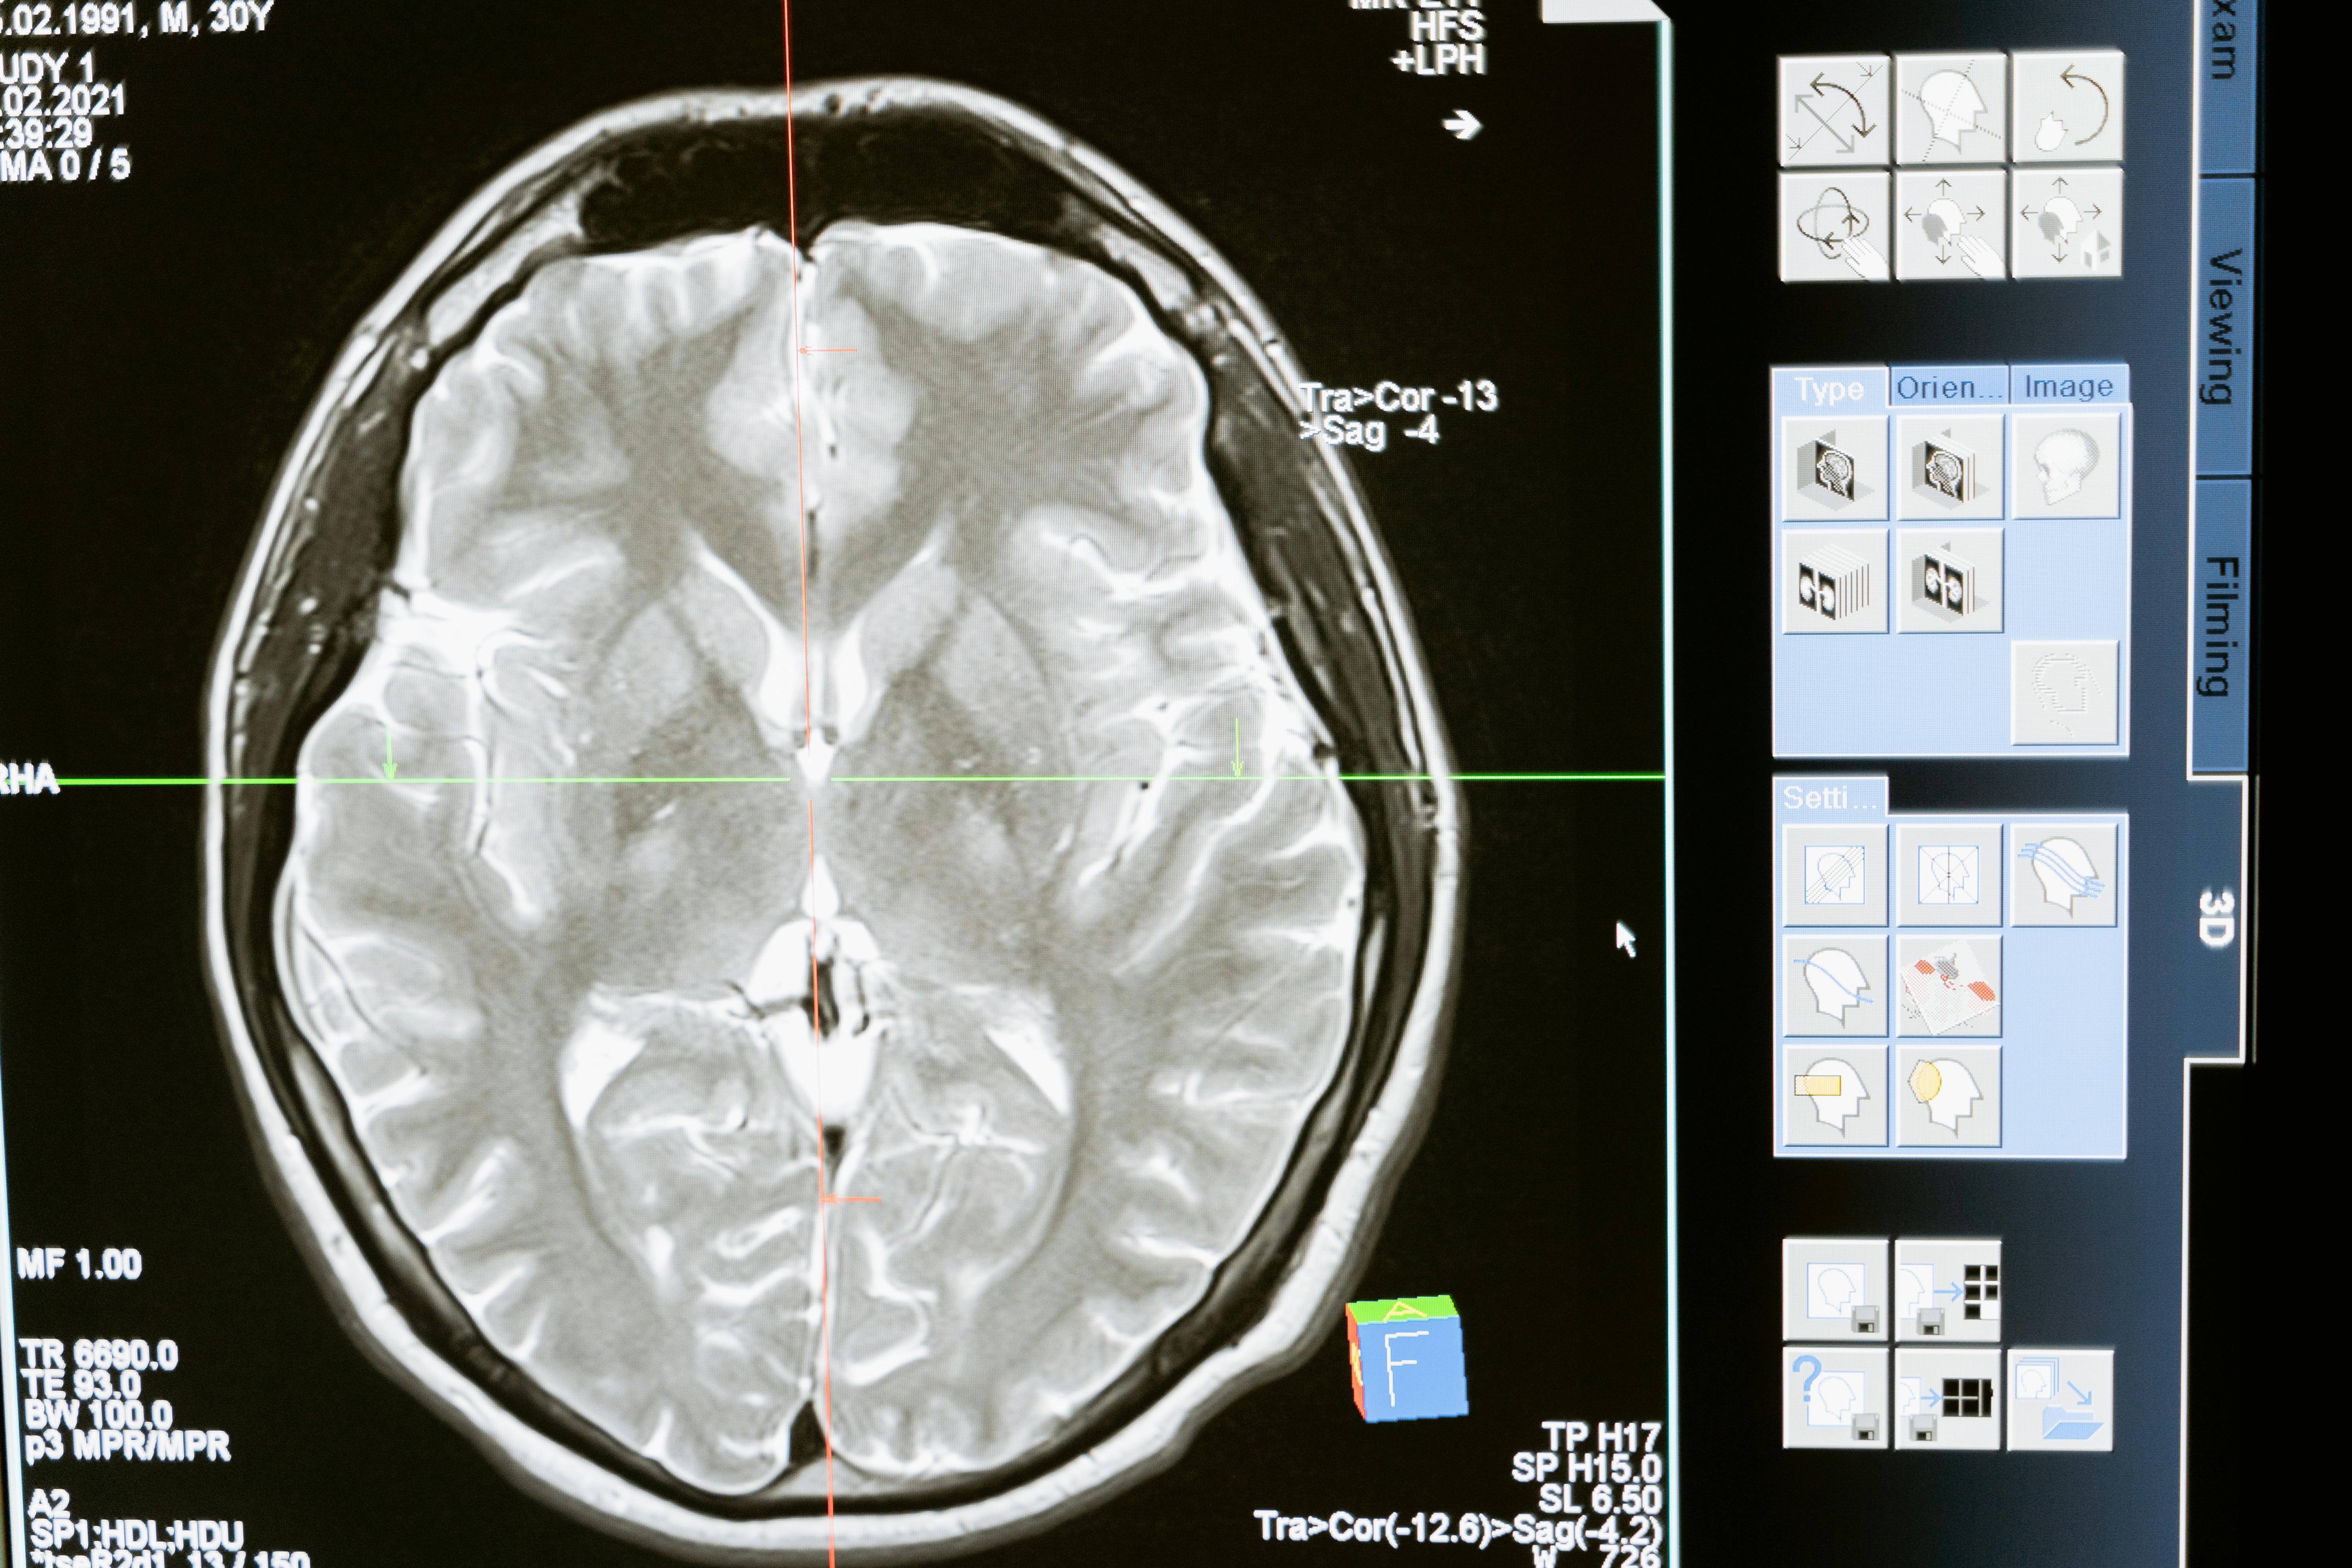

프로포폴은 뇌의 신경전달물질인 ‘가바(GABA)’ 수용체에 작용해 뉴런의 활동을 억제함으로써 뇌의 과도한 흥분 상태를 낮추고 진정을 유도한다. 가바는 뇌에서 억제성 신경전달물질로 작용하는데, 프로포폴은 이러한 가바 수용체의 민감도를 높여 뉴런 사이의 신호 전달을 억제한다. 그 결과, 뇌는 차분한 상태로 진입하며 의식은 점점 흐려진다.

연구팀은 원숭이에게 프로포폴을 투여한 후 1시간 동안 시각, 청각, 공간 인식, 실행 기능 등 뇌 피질의 네 영역에서 뉴런의 활동을 관찰했다. 정상적인 깨어 있는 상태에서는 외부 자극에 반응한 뉴런의 활동이 급격히 증가한 뒤, 빠르게 안정된 상태로 돌아갔다. 그러나 프로포폴이 투여되자 뉴런은 과도하게 흥분된 상태를 유지했고, 뇌가 원래 상태로 회복되는 데도 훨씬 더 많은 시간이 소요되었다.

특히 이러한 변화는 피험 동물이 점점 의식을 잃어갈수록 더욱 뚜렷하게 나타났다. 이 실험은 프로포폴이 단순히 뉴런을 ‘억제’하는 것이 아니라, 뇌 전체의 불안정성을 증가시킴으로써 의식을 끄는 것이라는 사실을 보여준다.